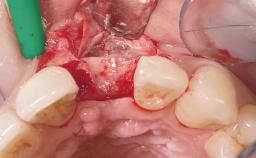

Late Flapless Placement of an Implant in a Maxillary Left Central Incisor Site

A 39-year-old male patient presented with a chief complaint of discomfort and gingival discoloration around his maxillary left central incisor. He was in good general health and was a non-smoker. His past dental history was significant because of the traumatic fracture of tooth 21 in a sporting accident at age 13. Initial dental treatment included endodontic therapy and a full-coverage restoration. The patient became symptomatic 5 years later, when structural failure of the tooth resulted in the dislodgment of the crown. Endodontic retreatment, apical surgery, and post-and-core restoration were performed.

Bone Volume Deficient horizontally, requiring prior grafting

Esthetic Risk High